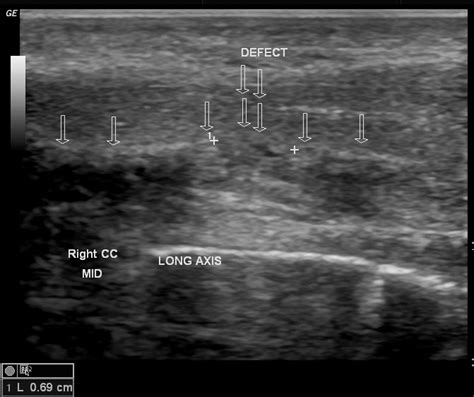

Penile fracture | Image | Radiopaedia.org

Penile fracture | Image | Radiopaedia.org from images.radiopaedia.org

Coitus and penile manipulations are common predisposing factors. Conclusions magnetic resonance imaging is of great value for the diagnosis of penile fracture. Being an examination required in urgency, it has to be included among the routinely planned experience in radiology.

P., saraf p.g., catanese, r. It is a rupture of corpora cavernosa and penile sheath (tunica albuginea) caused by trauma to an erect penis. It is a rupture of penile tunica albuginea of the corpora cavernosa or spongiosum caused by trauma to an. Rarer symptoms of a penile fracture include swelling in the. De luca f, garaffa g, falcone m, et al. Penile fracture may be defined as traumatic disruption of the tunica albuginea and enclosed corpus cavernosum as a result of blunt trauma to the erect penis. A penile fracture is a rare urological emergency which warrants prompt surgical intervention in order to restore form and function. Penile fractures happen only when you have an erection. Coitus and penile manipulations are common predisposing factors. The man feels significant pain. Conclusions magnetic resonance imaging is of great value for the diagnosis of penile fracture. Penile fracture occurs with a cracking sound. Department of radiology, hasheminejad kidney center (hkc), iran university of medical sciences, tehran, iran. Imaging findings when present with a history are diagnostic of this condition. Penile fracture after 9 hours. A penile fracture is a tearing of the tissue surrounding the corpus cavernosa in the penis. In most cases, a penile fracture is caused by a mild or significant tear to the tunica albuginea within the penis.